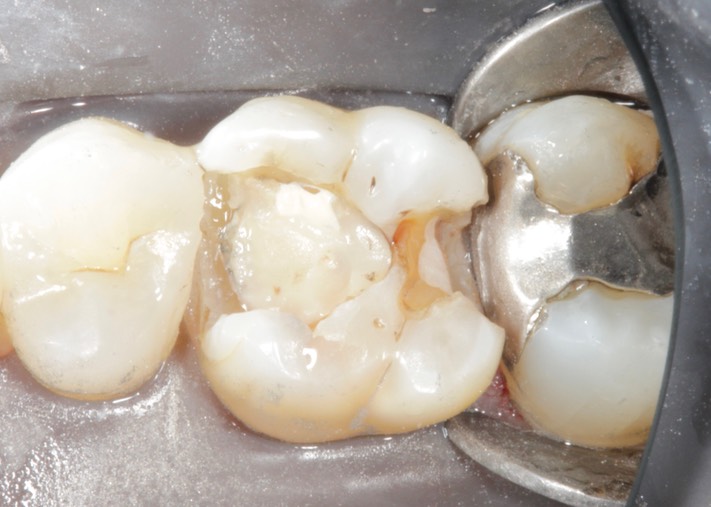

Gary Umeda #3 caries removal